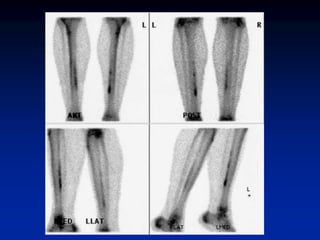

Shin Splints (Periostitis)

• exercise induced pain along medial or

posteromedial aspect of tibia

• associated with increased tracer uptake

• >1/3 of bone length

• middle to distal tibia

• usually bilateral (not necessarily symmetrical)

• microperiosteal tears (via Sharpey’s fibers)

• positive finding does not predict further injury

• Hyperperfusion and hyperemia are

typically present in acute stress fracture.

• Unlike in stress fractures, angiograms and

blood pool images are usually normal in

shin splints. Delayed bone images reveal

longitudinally oriented linear areas of

increased uptake of varying intensity that

involve one-third or more of the posterior

tibial cortex

Shin Splints (Periostitis) •exercise induced pain along medial or posteromedial aspect of tibia • associated with increased tracer uptake • >1/3 of bone length • middle to distal tibia • usually bilateral (not necessarily symmetrical) • microperiosteal tears (via Sharpey’s fibers) • positive finding does not predict further injury

• Hyperperfusion andhyperemia are typically present in acute stress fracture. • Unlike in stress fractures, angiograms and blood pool images are usually normal in shin splints. Delayed bone images reveal longitudinally oriented linear areas of increased uptake of varying intensity that involve one-third or more of the posterior tibial cortex